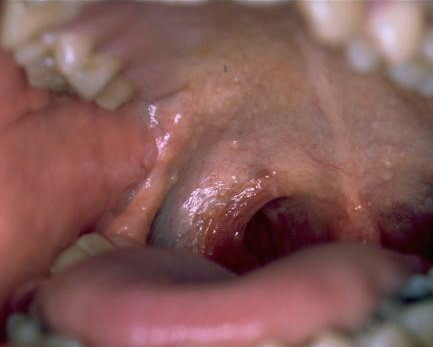

Hyalinosis Cutis et Mucosae=تنكس هياليني جلدي ومخاطي